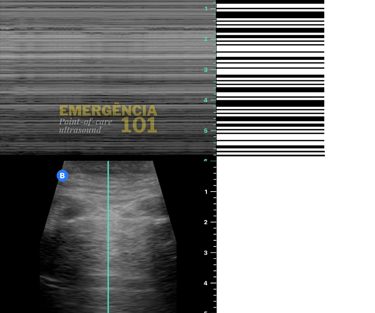

Em algumas situações, pode ser difícil visualizar se há ou não deslizamento pleural pelo modo B do ultrassom, como na avaliação dos ápices pulmonares, que são regiões naturalmente menos ventiladas, e/ou em pacientes com movimentos respiratórios menos intensos (imagine um paciente intubado com sedação profunda e volume corrente pequeno), nesses casos é possível utilizar o modo M (motion) do ultrassom para registrar o movimento da pleura, gerando dois sinais característicos:

Sinal da areia da praia: presença de deslizamento pleural. (figura 7b)

Sinal do código de barras: ausência de deslizamento pleural. (figura 7c)

Figura 7c. Barcode sign (Sinal do código de barras no modo M), significando ausência de deslizamento pleural no campo pulmonar avaliado, não necessariamente causado por pneumotórax. Acervo pessoal do autor.